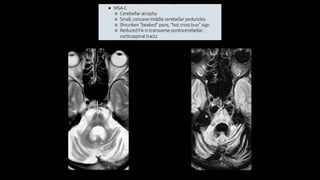

Atrofia de múltiplos sistemas

• Síndrome Parkinson Plus

• Atrofia de múltiplos sistemas (mais comum)

• Paralisia supranuclear progressiva

• Degeneração corticobasal